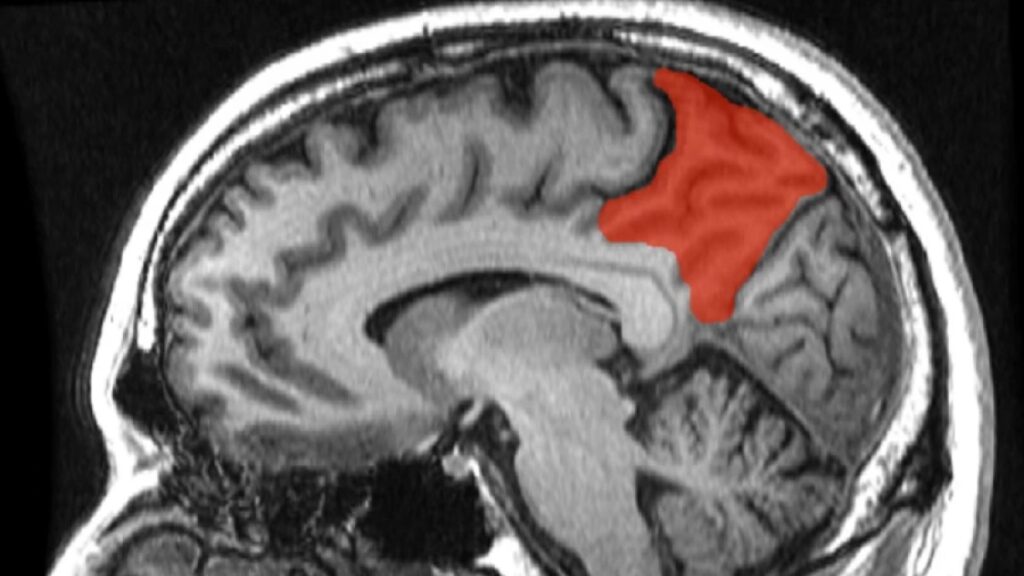

El precúneo, o precuña, es una parte del lóbulo parietal superior. Se encuentra alojado específicamente en la fisura longitudinal medial que separa los dos hemisferios cerebrales, lo que lo hace difícilmente accesible y visible sin técnicas de imagen avanzadas. A menudo se describe como la zona media de la corteza parietal superior. Sus límites anatómicos están bien definidos: hacia adelante, está delimitado por la rama marginal del surco cingulado; hacia atrás, por el surco parietooccipital; y hacia abajo, por el surco subparietal. Esta ubicación estratégica sugiere su rol como punto de conexión entre diferentes áreas cerebrales.

Anatómicamente, como se mencionó, el precúneo es una circunvolución pequeña con forma de cuña ubicada en la superficie medial del lóbulo parietal. Está claramente delimitado por los surcos parietooccipital (posteriormente) y el lóbulo paracentral (anteriormente). A pesar de su aparente simplicidad en la descripción anatómica gruesa, su organización interna es compleja, como reflejan sus subdivisiones funcionales. Estas subdivisiones, basadas en patrones de conectividad en estado de reposo, incluyen una región anterior sensomotora, una región centro cognitiva/asociativa, y una región visual posterior.